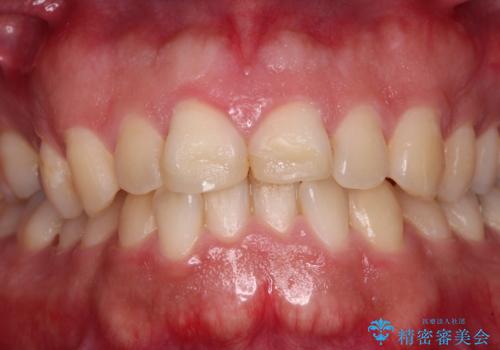

- 競技用自転車を運転中に転倒して前歯を強くぶつけ、欠けてしまったとのことで来院された患者様です。

近医にて欠けて部分を樹脂で修復してもらったものの、舌での感触が悪く、しみる感覚があるため、オールセラミッククラウンによる補綴治療を希望されていました。